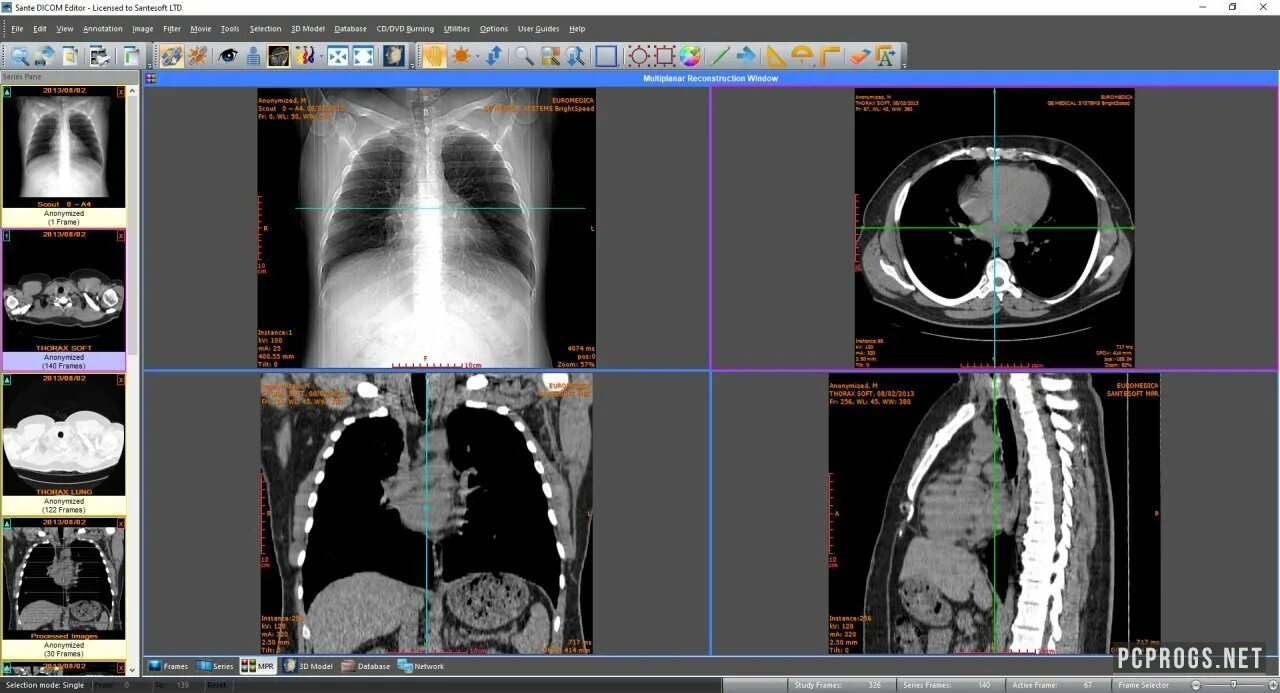

Радиант программа для кт